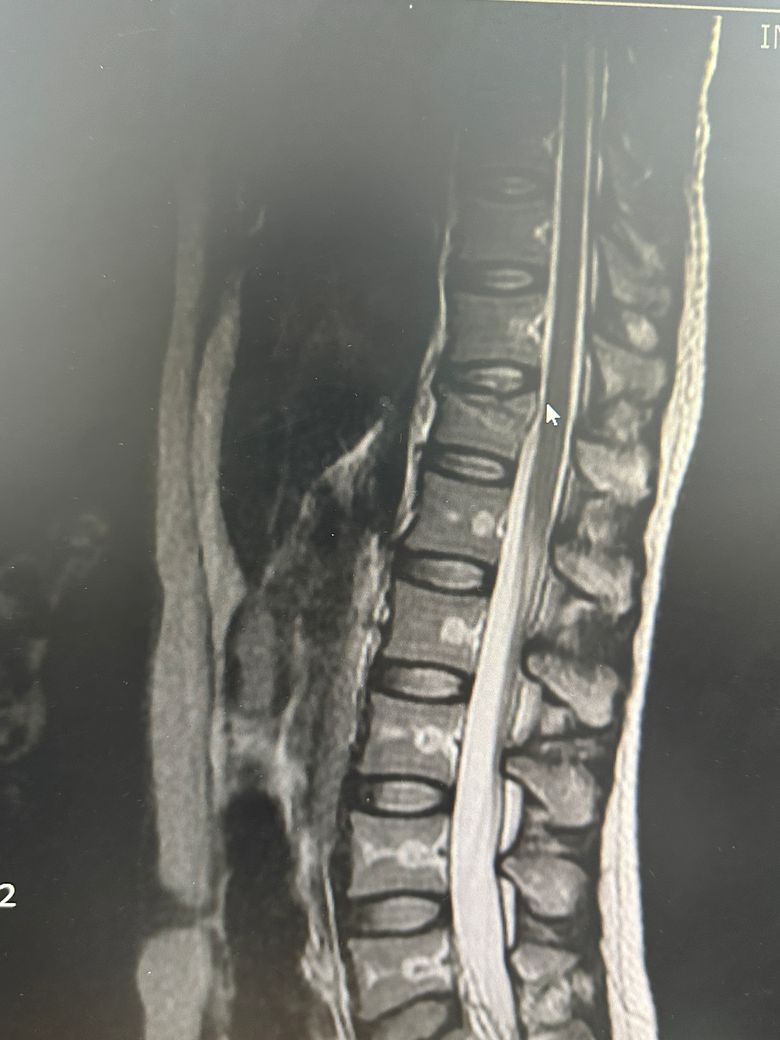

척추 mri 사진 봐주세요 안에 하얗게 보이는것

아랫부분들 직사각형 안에 가운데에 하얗게 심지처럼 보이는건 뭘까요?? 뼈가 약해진건가요?? 다른 사람들 척추 mri 보면 안저렇던데 불안해요 의사쌤에게 여쭤보는걸 까먹었네요

MRI 영상 왼쪽아래에 보면 이게 어떤 setting으로 촬영한건지가 나와있습니다.

T1, T2, T2 fat supression 이런식입니다.

이걸 알아야 하얗게 보이는게 뭔지 예상해볼 수 있습니다.

아마 다른 사람들에서 안보인 이유는 다른 세팅의 영상을 보셨기 때문일겁니다.

뼈가 약해져서 이렇게 보이는건 아니니 걱정 안하셔도 되겠습니다.

mri에서 뼈 속에 보이는 하얀 줄기 같은 모습은 보통 골수의 신호 변화로 정상적인 변이일 수도 있고 혈관, 지방 변성, 경미한 골수 부종처럼 특별히 병적이지 않은 경우가 많습니다.

척추체가 약해져서 골다공증처럼 무너진 경우는 대개 모양이 찌그러지거나 골절 흔적이 같이 보입니다. 사진만으로는 정확히 단정할 수 없지만 담당 선생님이 따로 설명하지 않았다면 심각한 소견은 아닐 가능성이 큽니다!